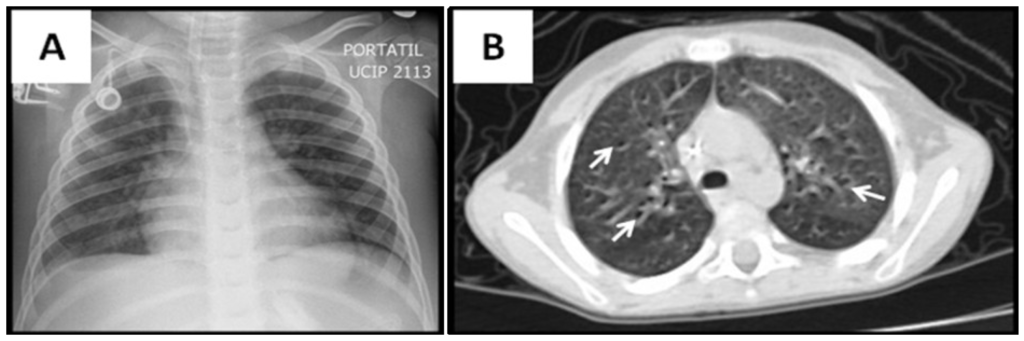

| Radiological variables | |

| Abnormal lung images, n (%) | 15 (100) |

| Ground-glass opacity, n (%) | 12 (80) |

| Consolidation, n (%) | 12 (80) |

| Atelectasis, n (%) | 6 (40) |

| Air trapping, n (%) | 5 (33) |

| Nodular pattern, n (%) | 3 (20) |

| Reticular pattern, n (%) | 1 (6) |

| Tree-in-bud pattern, n (%) | 1 (6) |

3.2. Radiological Findings in CMV Lung Infection